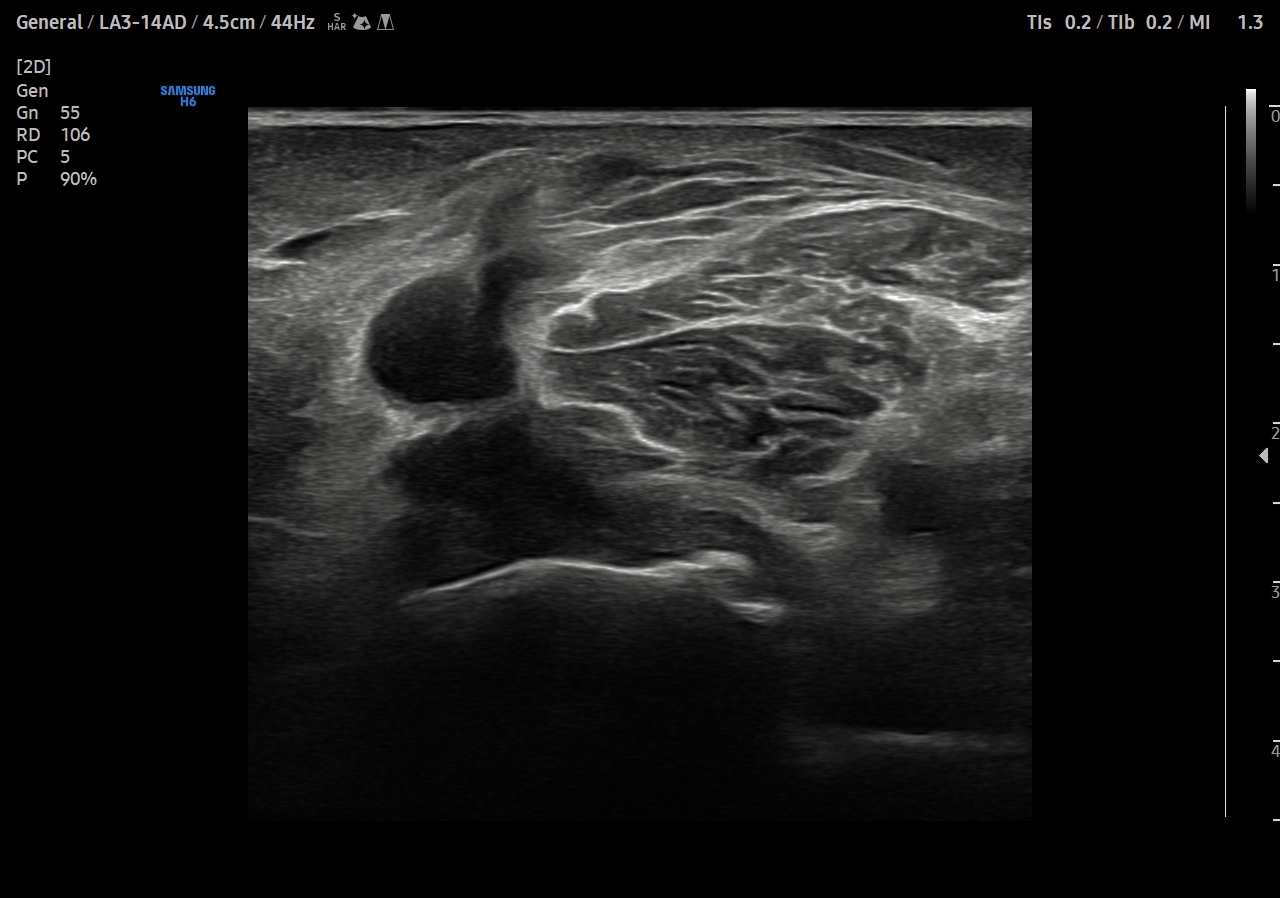

Se explora cara anterior, lateral y medial de rodilla sin hallazgos significativos. En cara posterior se explora el hueco poplíteo donde se visualiza en corte transversal una estructura hipoecoica con la base, el cuello entre el tendón del semimembranoso y el tendón de la cabeza medial del gemelo interno y el cuerpo. Sin signos de complicación. Permeabilidad del sistema venoso profundo.

Quiste de Baker.